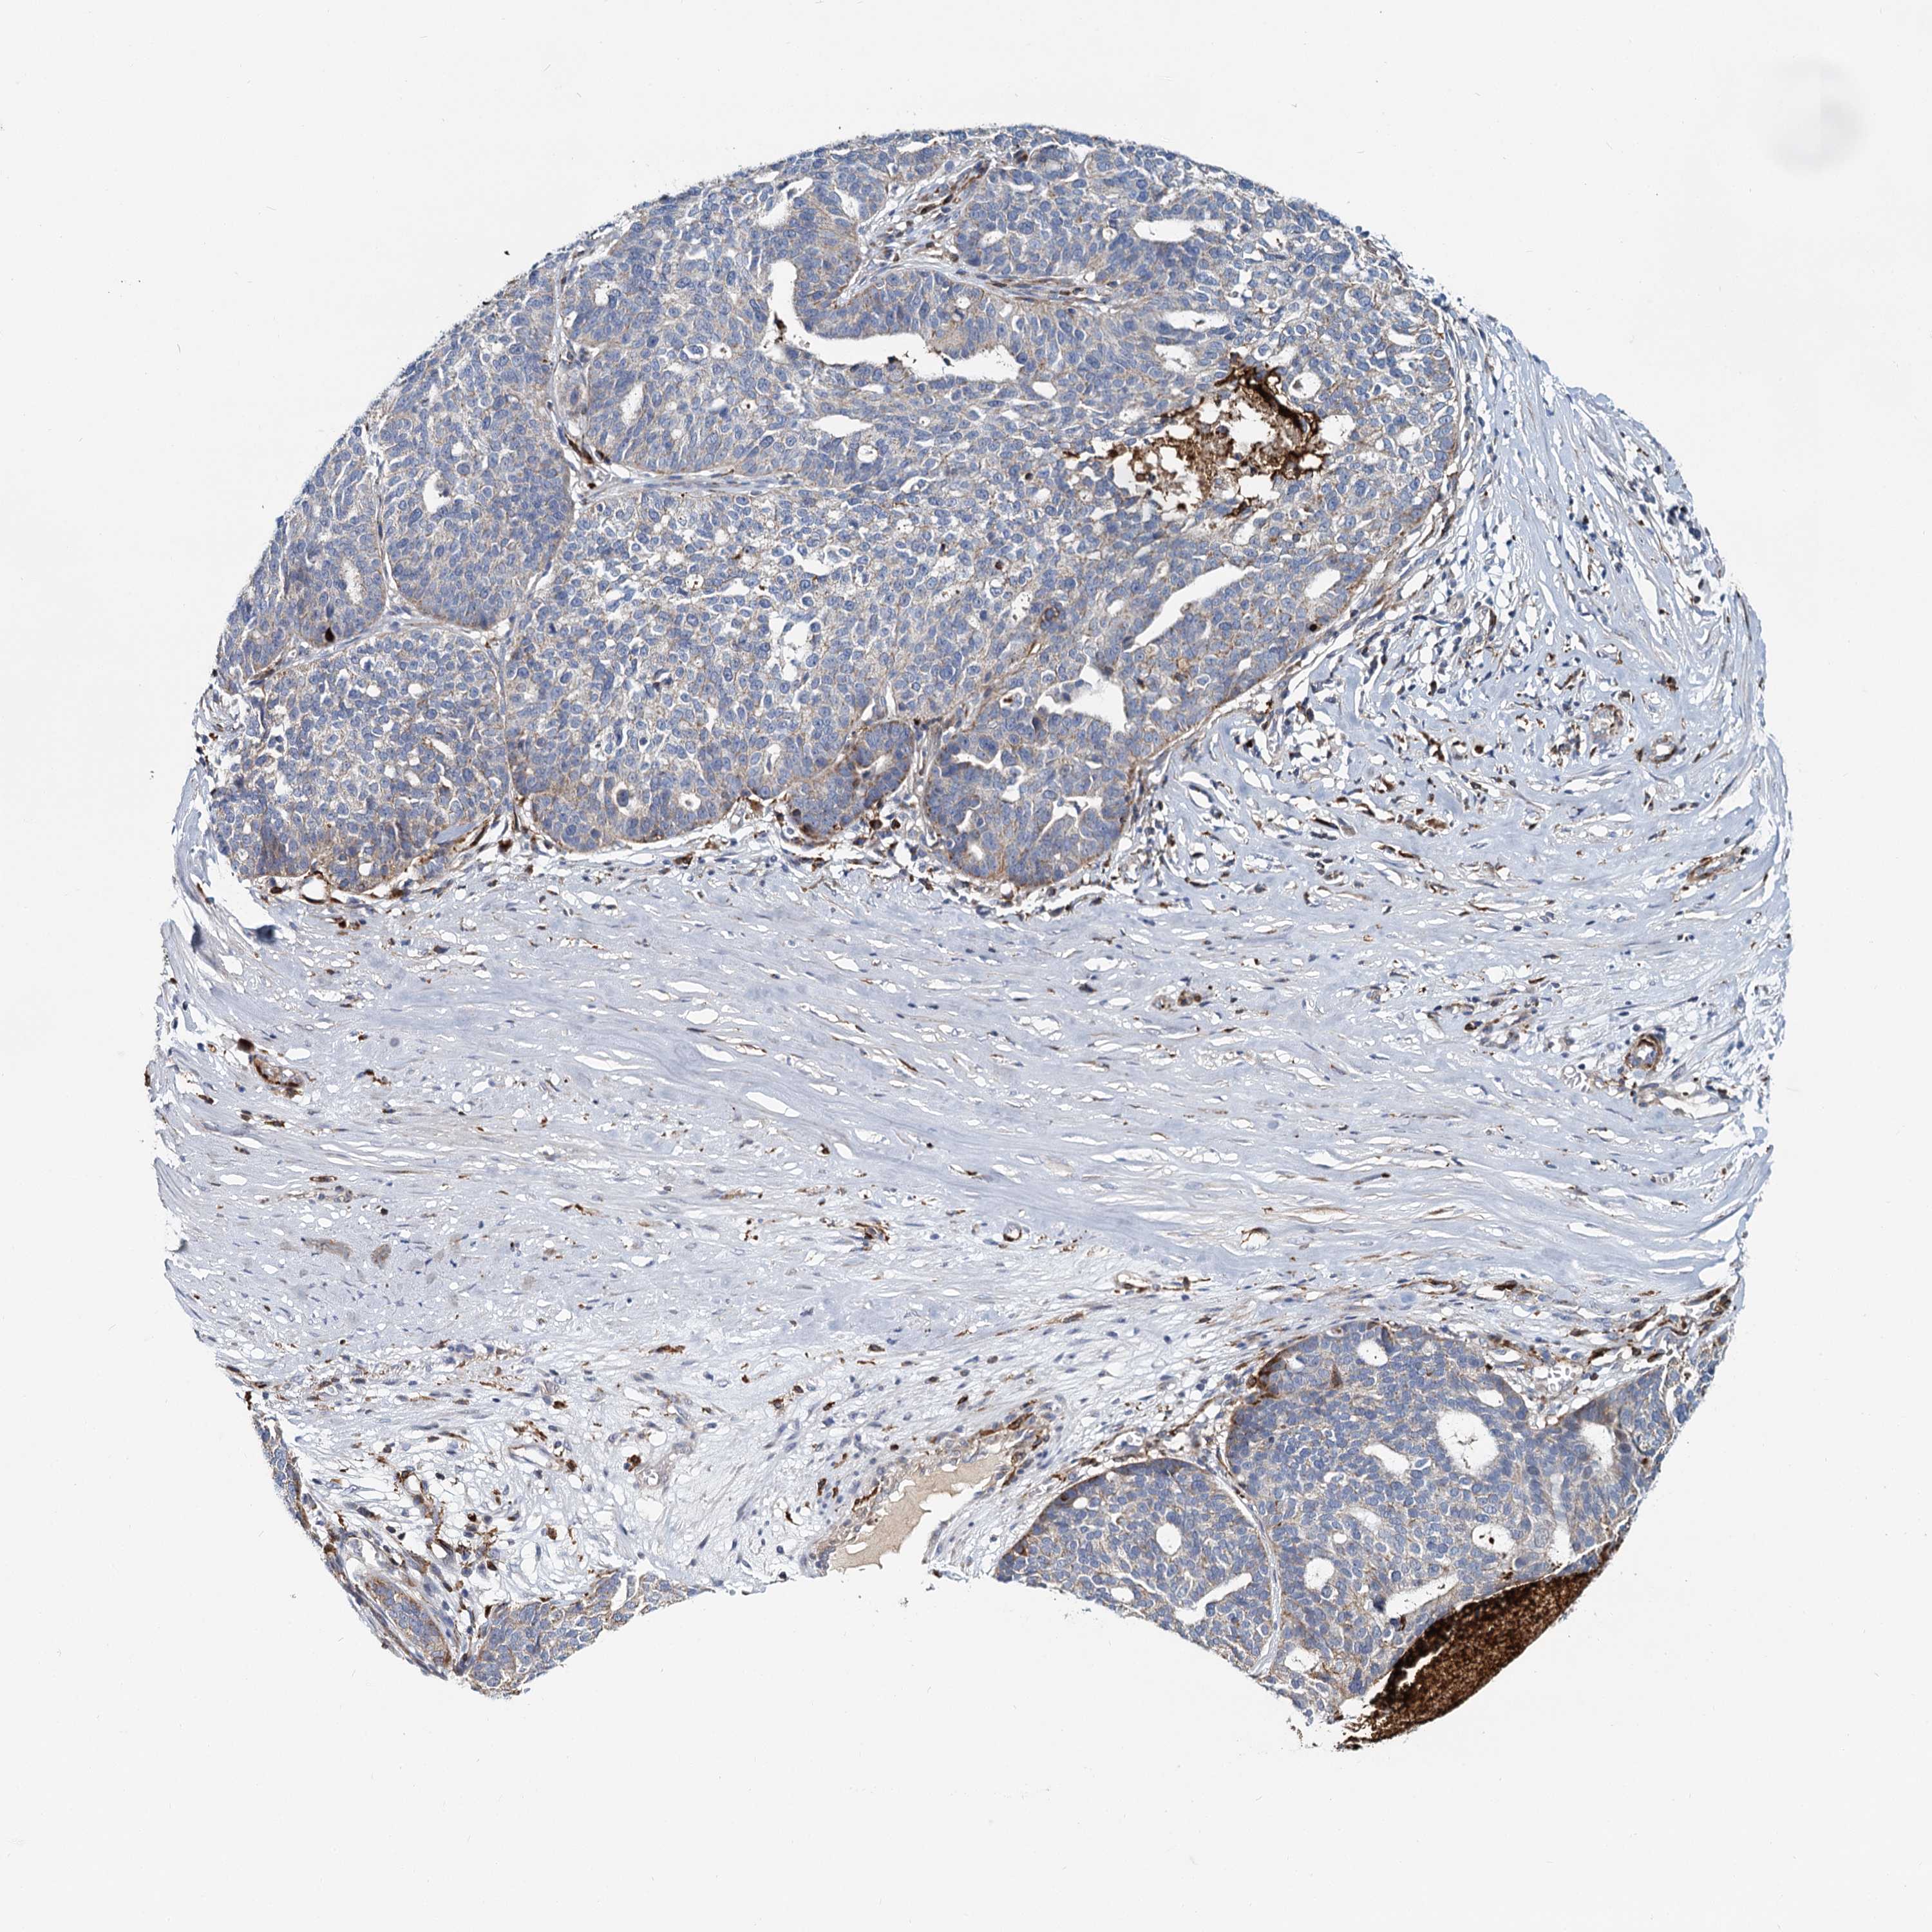

OVARIAN CANCER - Protein expressioni

A mouse-over function shows sample information and annotation data. Click on an image to view it in a full screen mode. Samples can be filtered based on level of antibody staining by selecting one or several of the following categories: high, medium, low and not detected. The assay and annotation is described here.

Note that samples used for immunohistochemistry by the Human Protein Atlas do not correspond to samples in the TCGA dataset.

Antibody stainingi

Antibody staining in the annotated cell types in the current human tissue is reported as not detected, low, medium, or high, based on conventional immunohistochemistry profiling in selected tissues. This score is based on the combination of the staining intensity and fraction of stained cells.

Each image is clickable and will lead to virtual microscopy that enables deeper exploration of all samples and also displays staining intensity scores, fraction scores and subcellular localization as well as patient and tissue information for each sample.

Antibody HPA039349

Staining

High

Medium

Low

Not detected

Intensity

Strong

Moderate

Weak

Negative

Quantity

>75%

75%-25%

<25%

None

Location

Nuclear

Cytoplasmic/membranous

Cytoplasmic/membranous,nuclear

Cystadenocarcinoma, serous, NOS

Carcinoma, endometroid

Cystadenocarcinoma, mucinous, NOS

Carcinoma, NOS